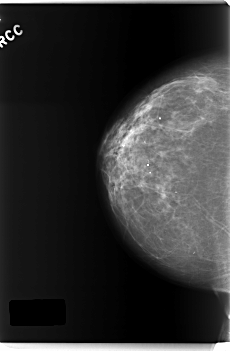

C_0218_1.RIGHT_MLO

RIGHT_MLO LINES 5872 PIXELS_PER_LINE 3920 BITS_PER_PIXEL 12 RESOLUTION 50 NON_OVERLAY